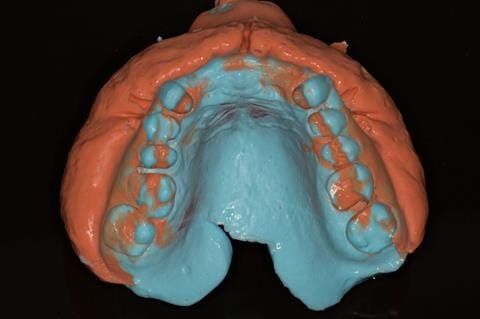

Following consultation and second discussion appointment the patient chose to have option 3 namely, a maxillary cobalt chromium based partial denture/protective occlusal splint. The clinical situation and treatment process is shown in detail below with photographs. The patient was successfully rehabilitated with this and her quality of life considerably improved. The clinical work was provided by Finlay and the technical work by Rowan.